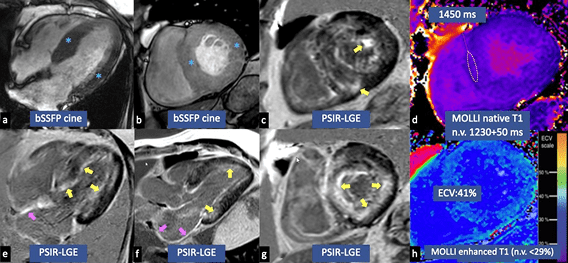

Bei extrakardialer Biopsie kann die Diagnose bestätigt werden, sofern sie von charakteristischen Merkmalen im ECHO oder c-MRT begleitet ist.

In der Biopsie ist die Herzamyloidose gekennzeichnet durch extrazelluläre Ablagerungen fehlgefalteten Proteins, begleitet von krankheitstypischen histologischen Eigenschaften einer grünen Doppelbrechung bei Betrachtung in kreuzpolarisiertem Licht nach Kongorotfärbung.6